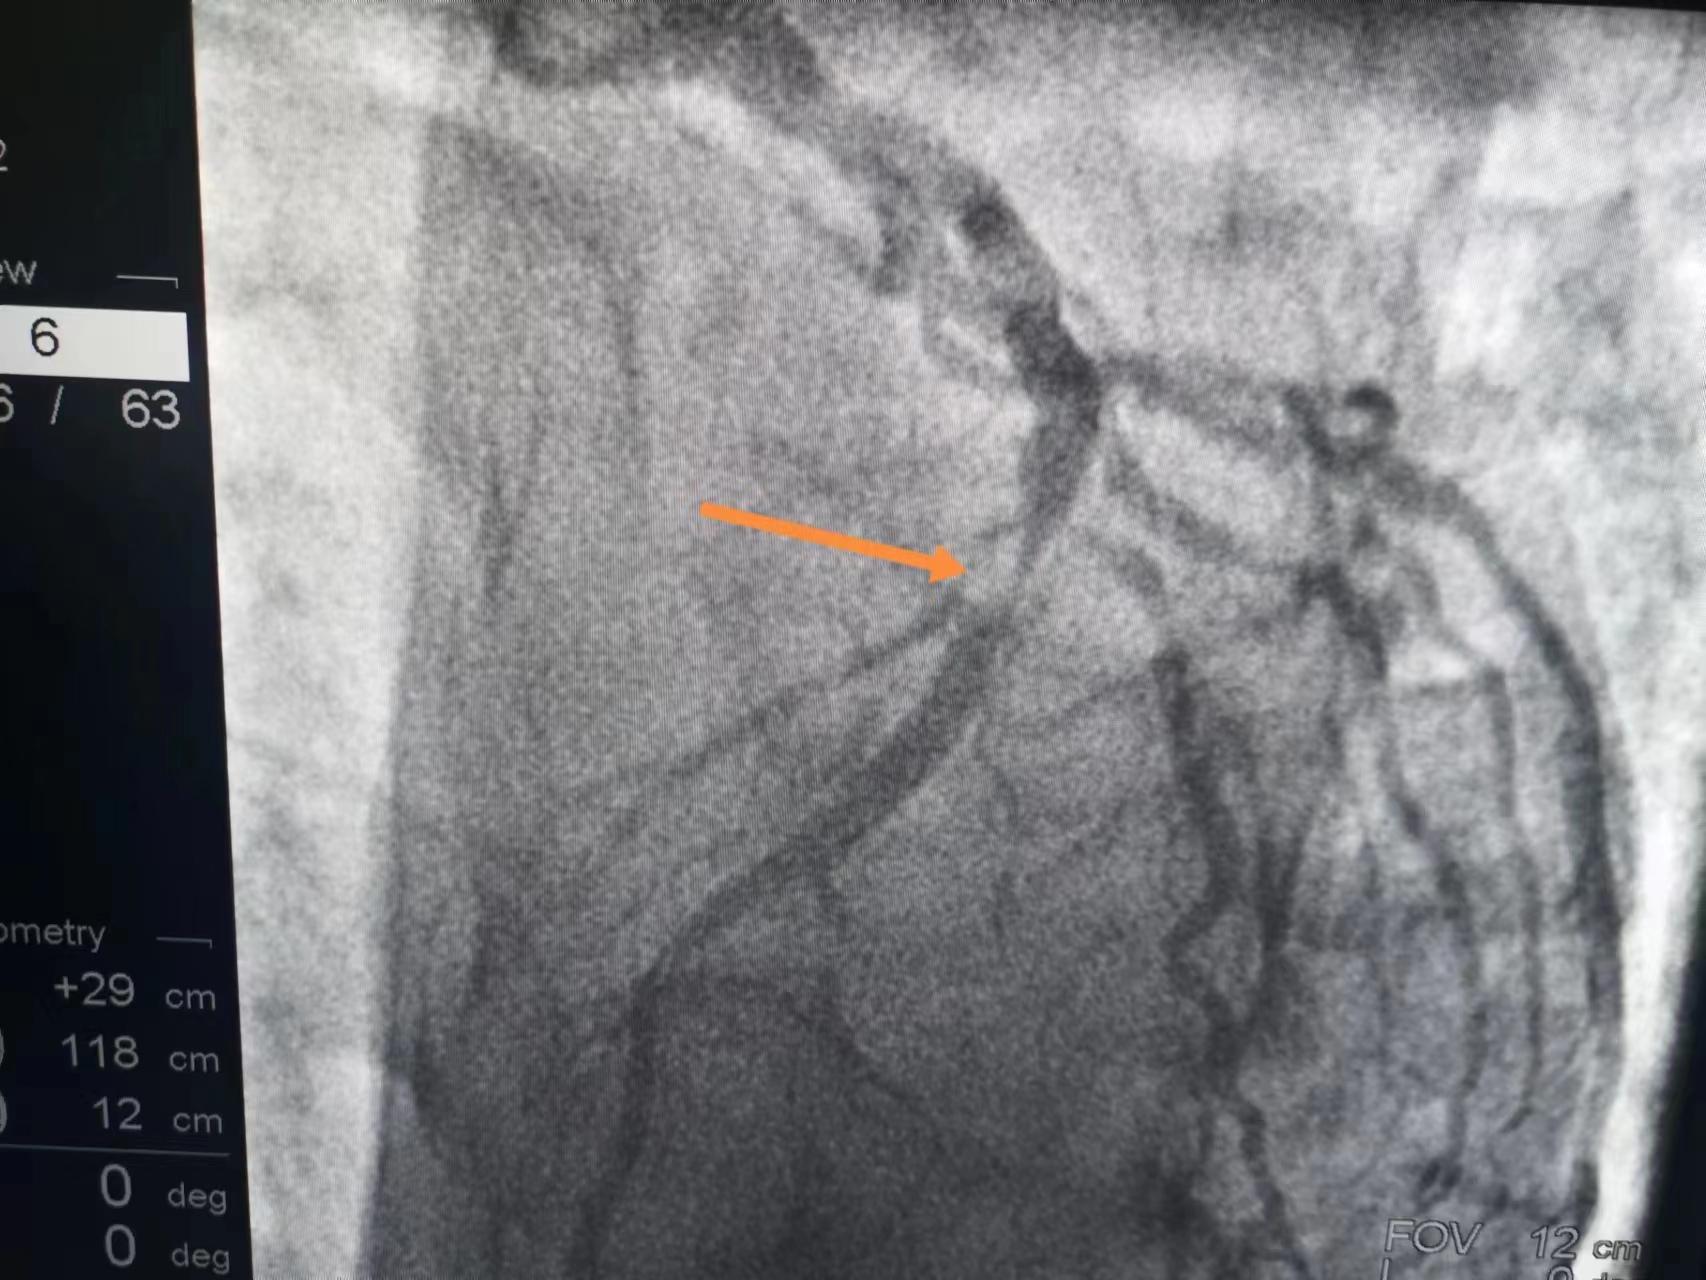

程先生被转至我们医院,造影发现,大家可以看到,心脏左侧的大血管中段有一个严重的狭窄,但血流是通畅的。这就说明溶栓成功了,所以非常感谢溶栓的医院。

大家也可以直观地看到,溶栓成功后的血管,即使血流恢复,但固定狭窄还是非常严重的,这种狭窄心肌缺血心绞痛的风险很大,而且心肌梗死风险也很大,所以还是植入了一枚支架,做完支架大家再看这血管,管腔完全恢复了,那么以后保养好,就不会心绞痛,心肌梗死的风险也会大大降低。